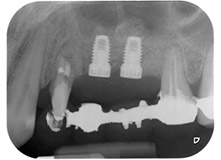

radiografía posoperatoria

Fig. 16: La radiografía posoperatoria muestra ambos implantes en sus posiciones correctas, con material sustituto óseo alrededor de los ápices procedente de la elevación interna del seno. También hay material visible alrededor de las raíces de la pieza 24 procedente del procedimiento de GTR.